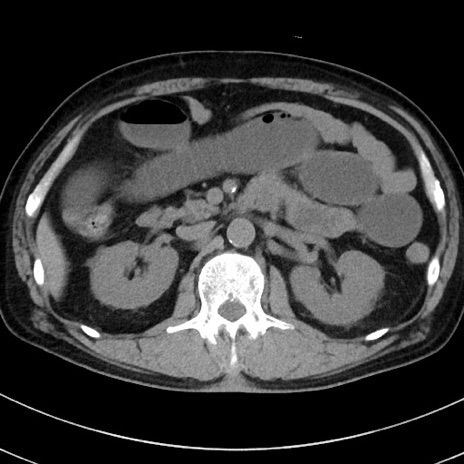

冠状断像

【症例】70歳代 男性

【主訴】腹痛・嘔吐

【現病歴】昨晩より、嘔吐・腹痛あり。今朝になっても嘔吐あり。来院。

【既往歴】心臓バイパス手術、開腹胆摘、腸閉塞

【身体所見】BP 107/71mmHg、HR 116/min、腹部:平坦、軟、下腹部に軽度圧痛あり。反跳痛なし。

【データ】WBC 15100、CRP 0.32